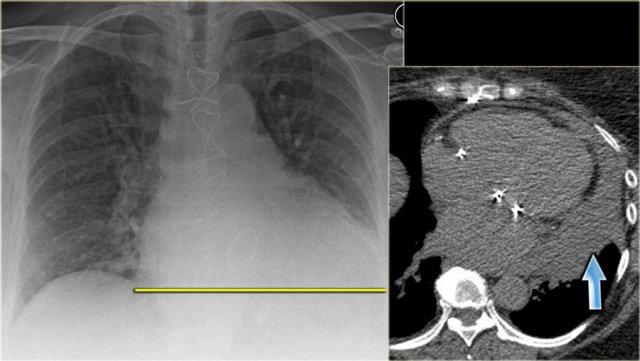

Hình bên trái là bệnh nhân vừa được phẫu thuật thay van tim.

Bóng tim lớn, có thể là hệ quả của tim to (cardiomegaly).

Do tiền sử phẫu thuật tim gần đây, khả năng tràn dịch màng ngoài tim đã được đặt ra và được minh họa rõ ràng trên hình ảnh CT.

Hình bên trái là một bệnh nhân khác có bóng tim lớn trên phim X-quang ngực do tràn dịch màng ngoài tim.

Tràn dịch màng ngoài tim được minh họa trên tái tạo CT mặt phẳng coronal.